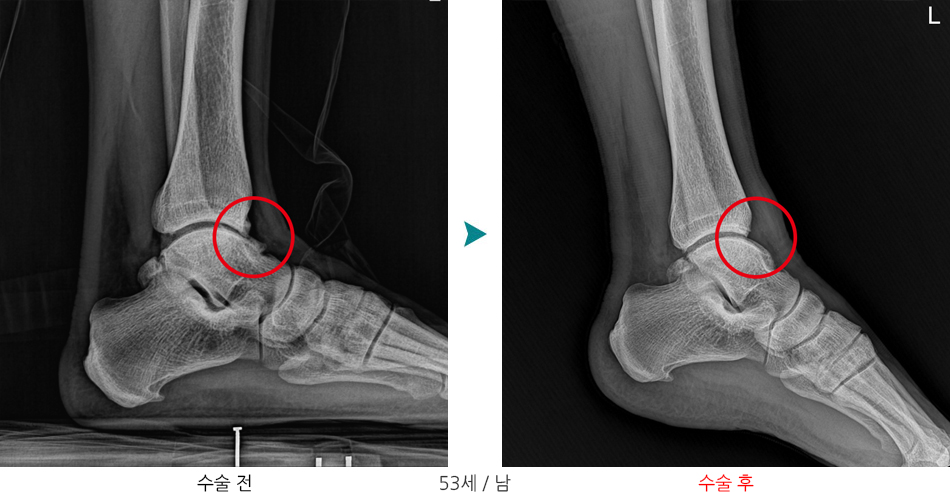

발목 전방충돌증후군

관절경하 골극절제술 / 연골성형술 및 미세절골술